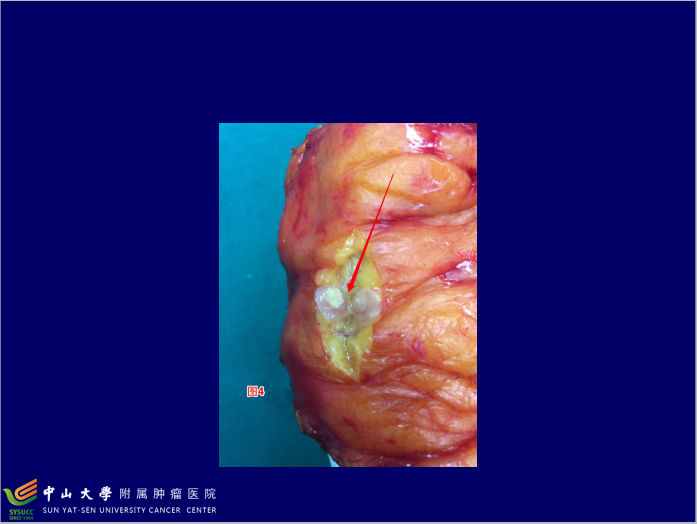

结直肠癌(colorectal cancer,CRC)是我国最常见的消化道恶性肿瘤之一,而且发病率和死亡率呈上升趋势。了解结直肠癌的分期旨在掌握其发展状况,以便指导制定治疗计划及评估预后。中山大学肿瘤医院(结直肠外科)陈功教授为您讲解CRC临床病理分期的几个问题。